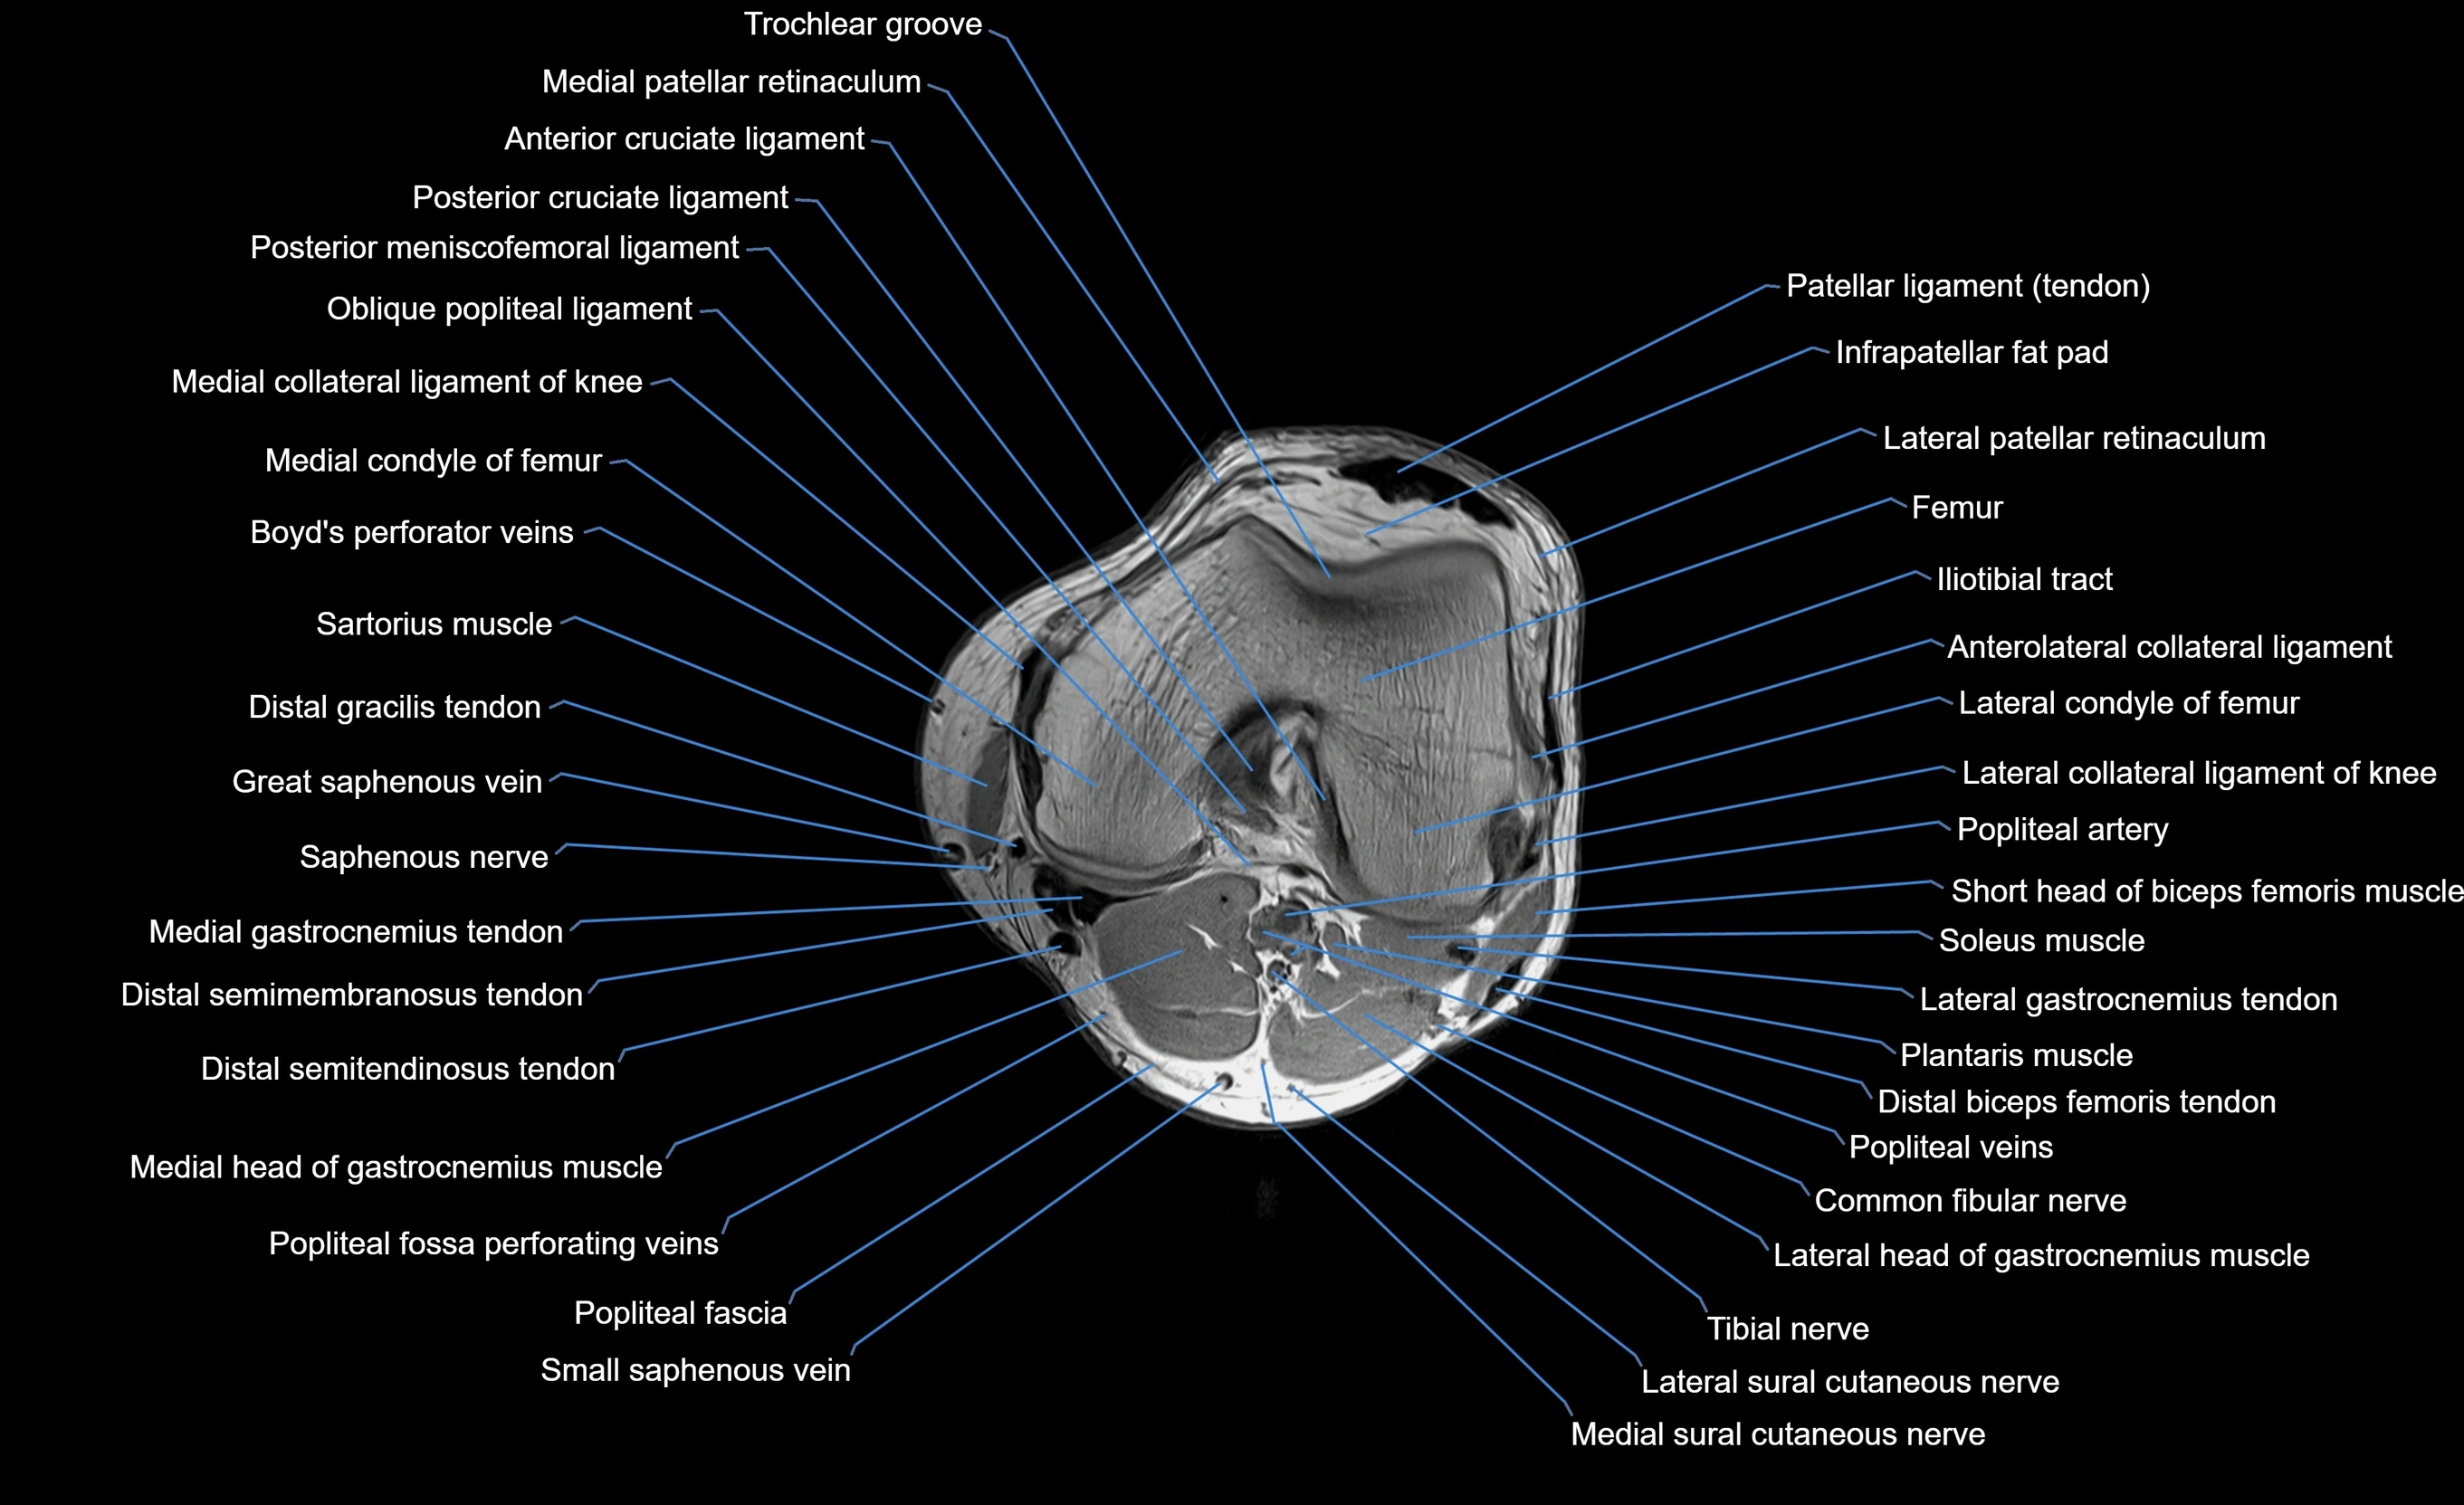

MRI image